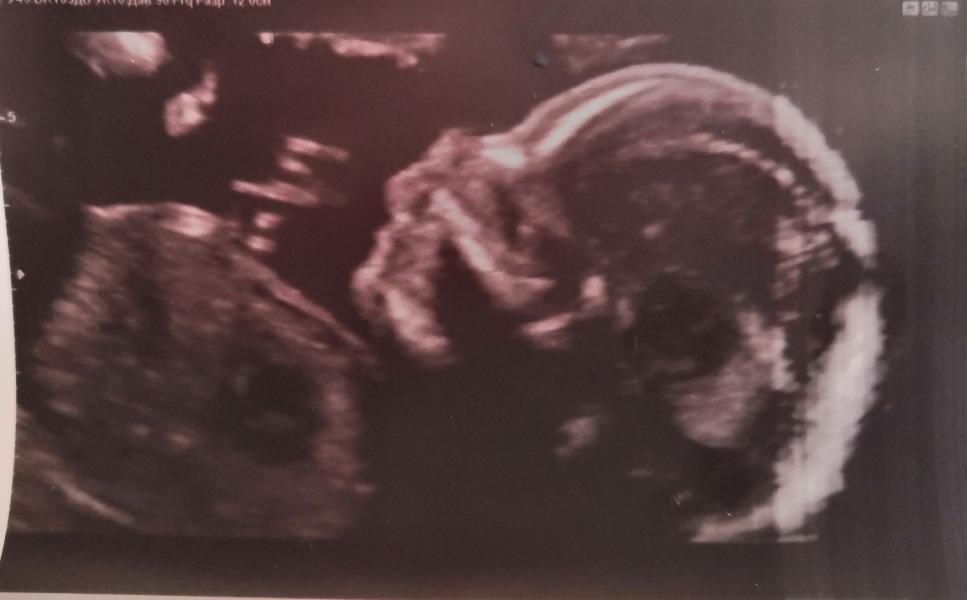

🤩🎉Наконец то я успокоилась и поводов переживать больше нет.. Сегодня было повторное УЗИ, т.к. чёртов 1 биохимический скрининг был не очень.. Всё хорошо с малышом🙏.. А этот анализ будь он проклят 🤣

Тоже после 1 скрининг, попала в группу риска, кровь не понравилась им и мой возраст 36лет. На всякий случай сделала прокол, все прошло хорошо, как и результат 😊 лучше все таки проверить и быть спокойной, хотя для тех у кого есть риск прерывания, нужно хорошо все взвесить.